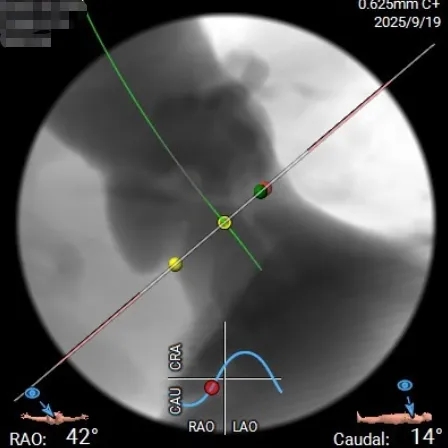

投照体位及瓣环角度分析

Angio

右窦中心

左右重合

右无重合

外周入路评估